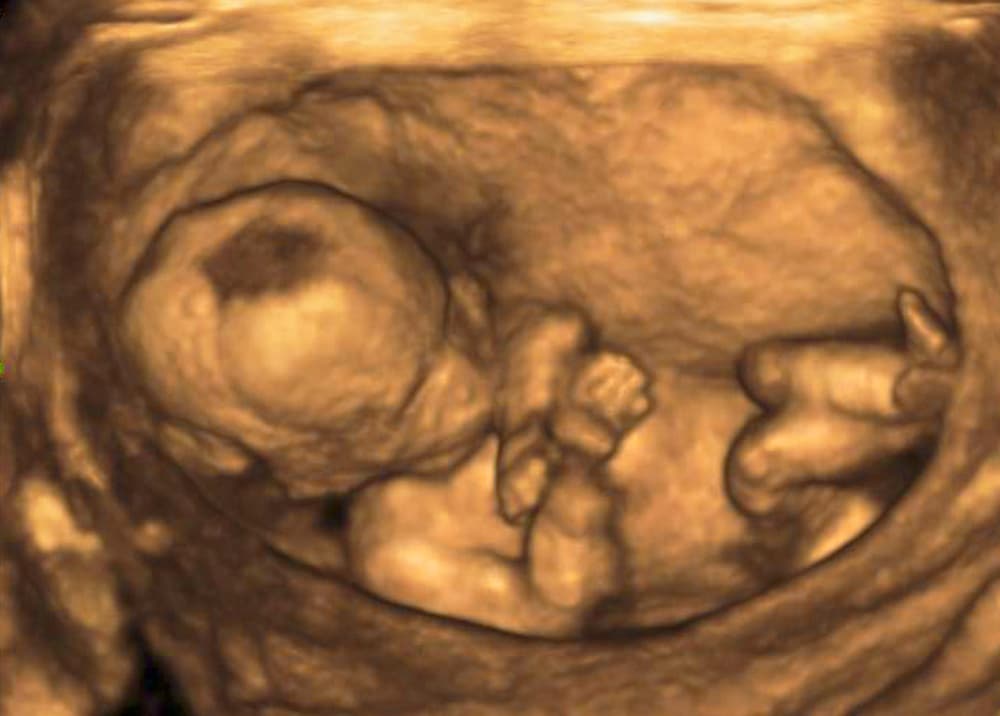

Si lo considera pertinente, también puede realizarte una ecografía para revisar el crecimiento de tu pequeño, así como un ultrasonido Doppler para observar el flujo sanguíneo hacia la placenta.

Este problema se puede presentar en cualquier punto del embarazo, aunque es más común que ocurra después del segundo trimestre. Generalmente se detecta en una ecografía.